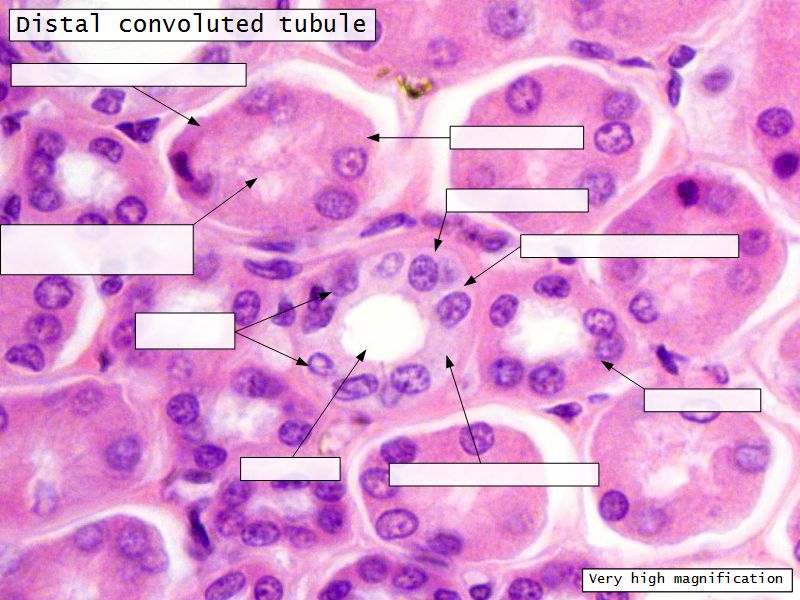

Continuation of descending and ascending tubuliDistal convoluted tubuli

- Joins collecting tubule

- Cuboidal epithelium

- Light stained

- Wide looking lumen

- Indistinct borders

Collecting tubule

- Cuboidal to columnar epithelium

- Distinct lateral borders